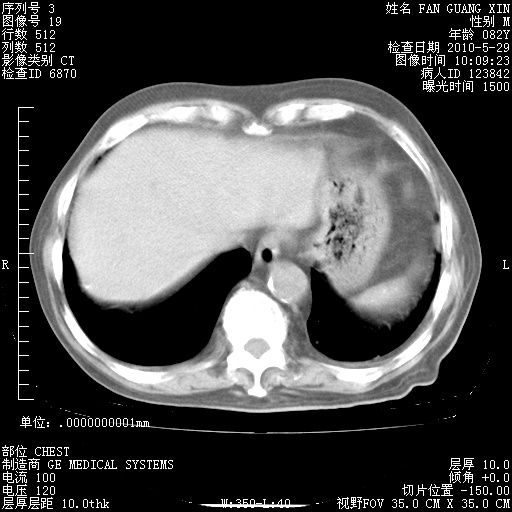

再治疗10天后的肺部CT 纵膈窗

从白细胞总数和中性比例看好像合并感染。肺部纹理好像比上次多,支气管炎?其他感染?

阅读此次胸部CT,肺间质渗出性改变较入院时有吸收。目前从体温、白细胞、中性分叶明显增高,肯定存在细菌感染(发生医院感染哦,若无消化道及泌尿系统等感染的依据,肺部感染可能大)。若你院头孢哌酮舒巴坦钠耐药率较高,同意你的方案,若48小时体温仍高,可考虑使用碳青霉稀类抗菌药物,同时可予超声雾化、注意滴数时加大液体量。白蛋白33.30g/L较低哦,需加强营养等支持治疗。